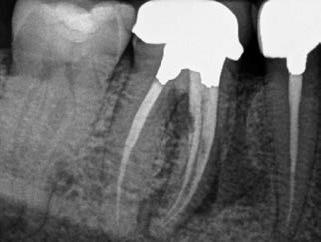

Egy 38 éves nőbeteg a korábban kezelt jobb felső második kisőrlőfogából (1.5) kiinduló mérsékelt fájdalom miatt jelentkezett rendelésünkön. A kórtörténetében jelen panasza szempontjából releváns információ nem szerepelt. A beteg a klinikai vizsgálat során vertikális kopogtatásra enyhe érzékenységet jelzett. A kérdéses fog körül mérhető szondázási mélység és a fogmobilitás fiziológiás volt. Periapicalis röntgenfelvételen egy, a fog gyökércsúcsán túl presszálódott betört gyökérkezelő műszerből származó eszközfragmentumot láttunk (2. a. ábra). A preoperatív CBCT-felvétel a buccalis csontlemez épségét igazolta (2. b-c. ábra). A fog revíziója öt hónappal korábban történt. A már előzőleg gyökérkezelt, gyökértömött, majd revideált 1.5-ös fog esetében a diagnózisunk periodontitis periapicalis symptomatica volt. A periapikális elváltozás kezelése érdekében navigált endodonciai mikrosebészeti beavatkozást végeztünk.

A felső állcsontról intraorális szkent (TRIOS) készítettünk, és az ezáltal kapott STL fájlt (2. d. ábra) a CBCT-felvétel során nyert DICOM fájlokkal a Zirkonzahn.Implant-Planner (Zirkonzahn) szoftverben egyesítettük. A sebészi sablont ebben a programban megterveztük, majd a Meshmixer (Autodesk) szoftver se-

gítségével tovább módosítottuk. Az így kapott sebészi sablon egyértelműen meghatározta a periapikális terület eléréséhez szükséges csontablak határait (2. e-f. ábra) Helyi érzéstelenítést követően teljes vastagságú mucoperiostealis lebenyt képeztünk, majd a buccalis csont feltárását követően (2. g. ábra) a sablon segítségével bejelöltük a preparálandó csontablak határait (2. h. ábra). A csontablak kialakítása során Piezotome CUBE LED kézi-darabot alkalmaztunk, majd a leemelését követően a betört eszközt megkerestük (2. i. ábra) és eltávolítottuk (2. j. ábra). A rezekciót ultrahangos megmunkáló fejekkel (ACTEON) végeztük, majd retrográd preparáció következett.

A retrográd gyökértömés elkészítése során TotalFill BC RRM Fast Set Putty-t (FKG) használtunk (2. k. ábra). A lebeny széleit 5/0-s Prolene varratokkal egyesítettük (2. l. ábra). A varratok a műtétet követően 72 órával kerültek eltávolításra. A beteg két évvel később kontrollröntgen készítése céljából érkezett rendelőnkbe. A vizsgálat során a fog tünetmentesnek és funkcióképesnek bizonyult (2. m. ábra).